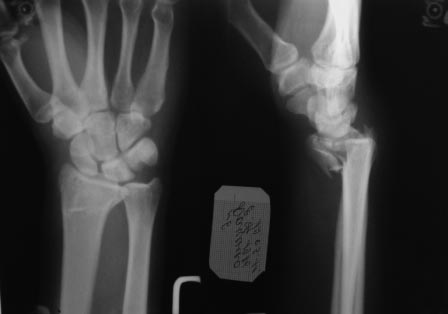

Re: перелом луча

Извините за позднее вмешательство в Вашу полемику. Хотелось начать по порядку. На мой субъективный взгляд одномоментного сочетание методов накостного и чрескостного остеосинтеза уменьшают достоинства обоих. Достоинства накостного остеосинтеза: более ранняя социальная реабилитация больного, т.к. не требуется специального ухода (как при использовании ЧКДО). Достоинство аппарата внешней дистракции - меньшая травматичность по сравнению с накостным остеосинтезом.

Что касается вариантов накостного остеосинтеза: возможно два варианта - остеосинтез волярной пластиной или фрагмент-специфическая фиксация отломков по Мedoff, но в связи с тем что перелом внутрисуставной очень часто требуется артротомия, т.к. наличие даже ЭОПа не обеспечивает точного восстановления суставной поверхности лучевой кости. Второй менее травматичный способ визуализации репозиции внутрисуставных отломков, признаный рутинным в ходе заседания EWAS в рамках FESSH 2010 (конгресс европейского общества хирургов кисти), проходивший в Бухаресте, это артроскопия кистевого сустава. Думаю данный способ вряд ли доступен в данном случае.

Остается как самый уместный способ - чрескостный остеосинтез с применением аппарата внешней фиксации: т.к. он весьма бюджетный и позволяет достичь необходимой репозиции.